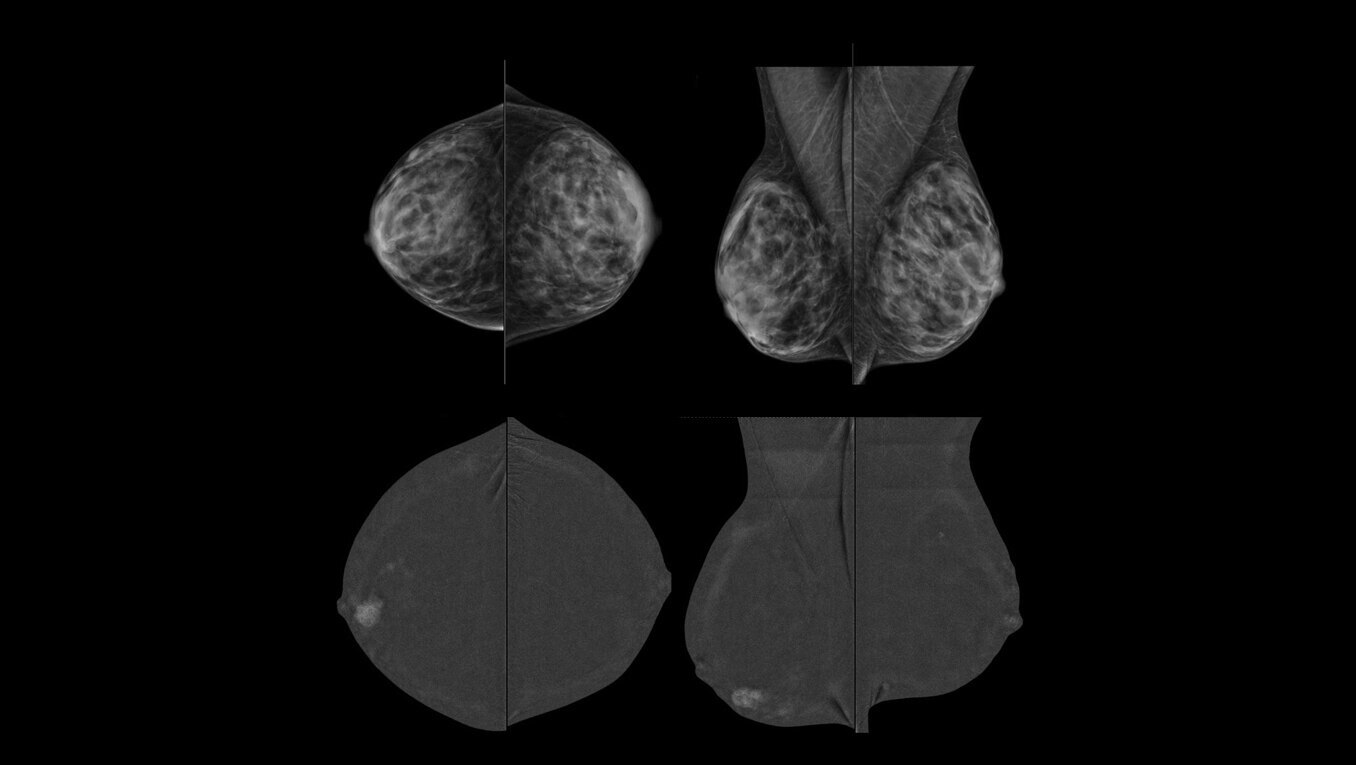

SenoBright™ HD

Contrast-Enhanced Mammography advanced application

Reduces the masking effect of breast tissue to reveal what matters1.